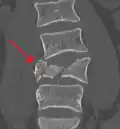

A burst fracture of L4 as seen on plane X ray -

A burst fracture of L4 as seen one plane X ray -